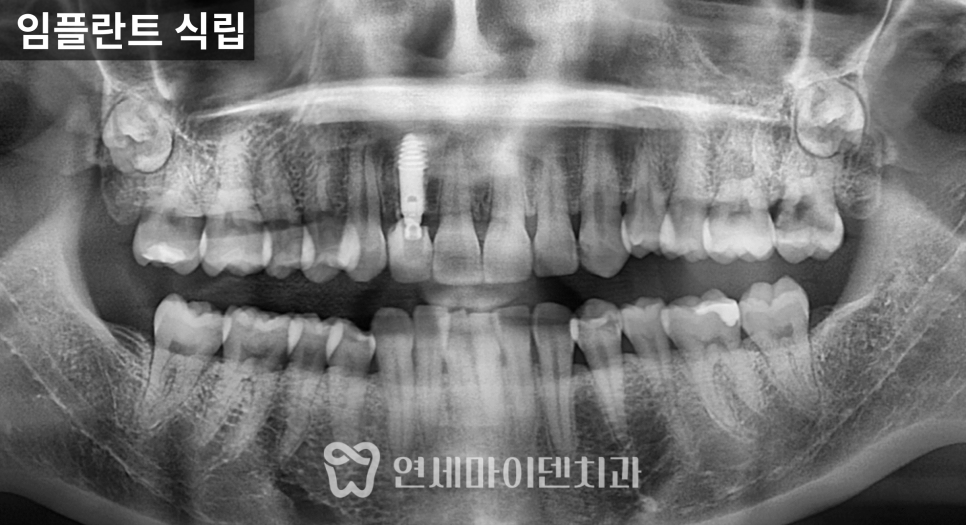

치료 전 방사선 사진을 보면

치아가 쓰러진 문제도 있었지만

무엇보다 뼈의 폭과 높이가

많이 줄어든 상태

였습니다.

잇몸도 전반적으로 약했고,

1차 수술: 발치, 염증 정리, 식립과 이식 동시 진행

첫 단계에서는

아래 1개, 위 2개

3개의 임플란트를 계획했습니다.

위쪽은 상악동이 내려와 있어

상악동 거상술과 뼈이식을 함께 시행한 뒤

그 공간에 임플란트를 식립했습니다.

아래쪽은 뼈 상태가 비교적 유지되어 있었지만

안정적인 고정을 위해

필요한 부위에 뼈이식을 병행했습니다.